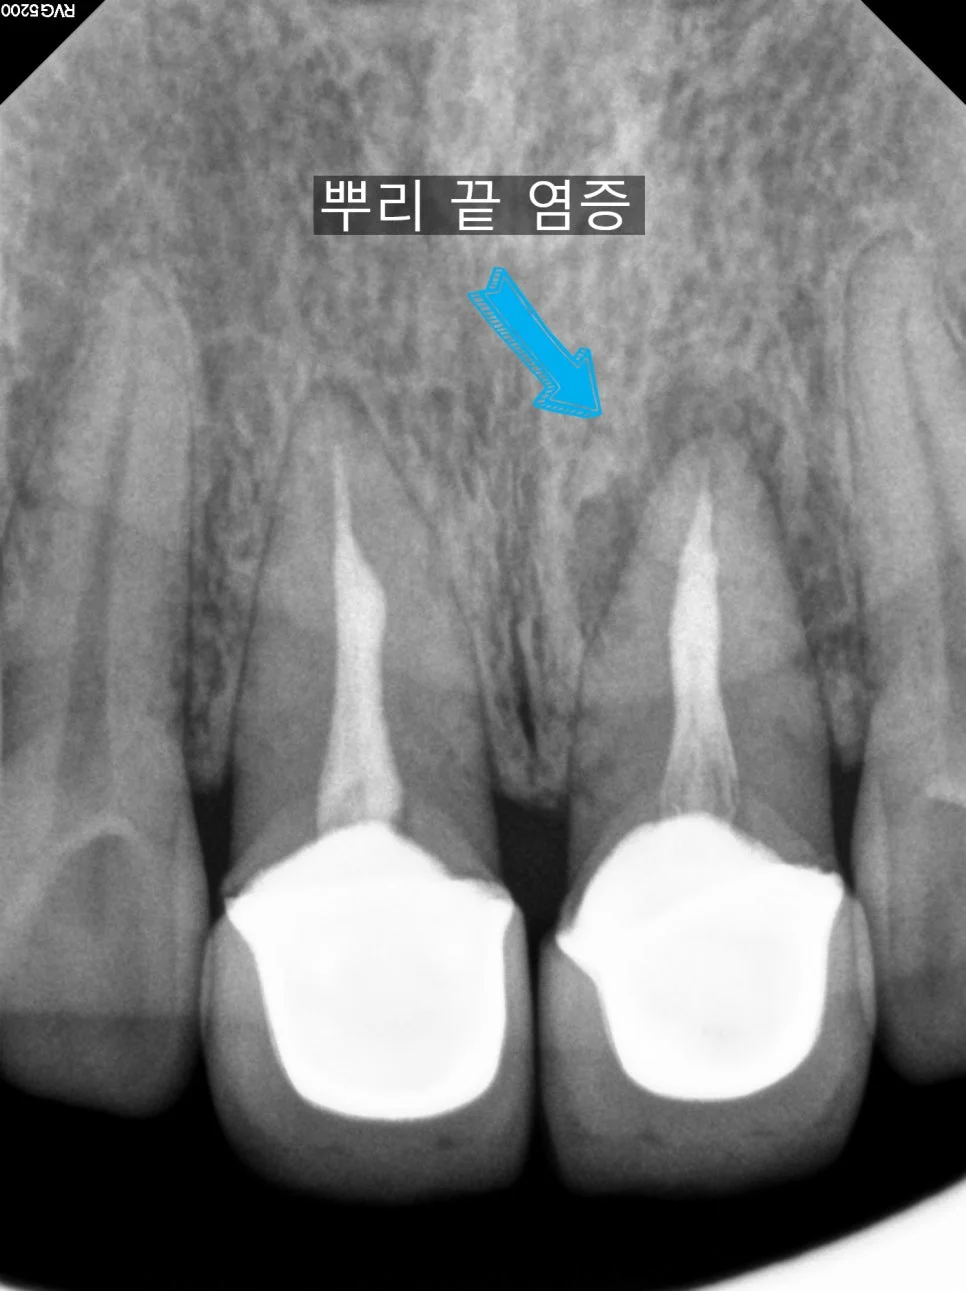

치근단 엑스레이 뿌리 끝 검은색 음영 염증 소견

좋은 진료를 정직하게 | 선한 영향력으로 더 나은 가치를 재신경치료 후기와 비용, 발치 판정 치아도 살릴 수 있을까? 강서구 마곡 서울쏙쏙치과 꿈꾸는 쏙쏙 치과의사 박상억입니다^^ 안녕하세요^^ 오늘은 신경치료 후 통증에 의한 재신경치료에 대해 알아볼 건데요^^ 신경치료를 한 지 한참 지난 치아가 어느 순간부터 불편하고 아프다면 오늘의 포스팅이 도움이 되실 거라 생각합니다~^^ 그럼 바로 시작해 보겠습니다! … 더 읽기